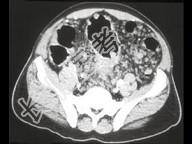

- 单项选择题男,15岁, 下腹疼痛不适,结合图像, 最可能的诊断是 ( )

A、结肠和系膜多发性血管瘤

B、结肠癌腹腔淋巴结转移

C、结肠淋巴瘤

D、假膜性肠炎

E、结肠溃疡性结肠炎